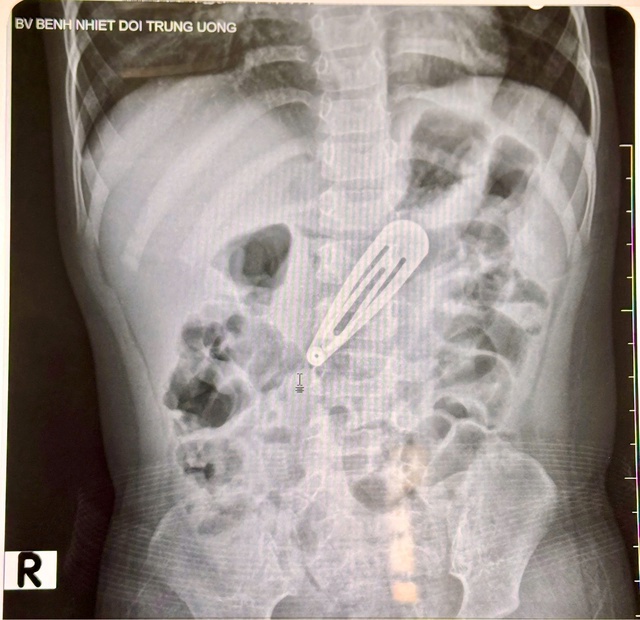

Sau khi thăm khám lâm sàng và chụp X-quang bụng, các bác sĩ ghi nhận hình ảnh một dị vật kim loại nằm trong ổ bụng, tương ứng vị trí dạ dày của bé. Bé nhanh chóng được chuyển sang Trung tâm Nội soi tiêu hóa và Thăm dò chức năng để tiến hành nội soi can thiệp lấy dị vật ra ngoài.

Hình ảnh chụp X-quang bụng của bé gái, phát hiện dị vật.

BS. CKI Tô Duy Thư cho biết, dị vật là chiếc kẹp tóc kim loại, dẹt, đầu tù, cạnh sắc, nằm ở vùng thân vị (phần giữa của dạ dày).